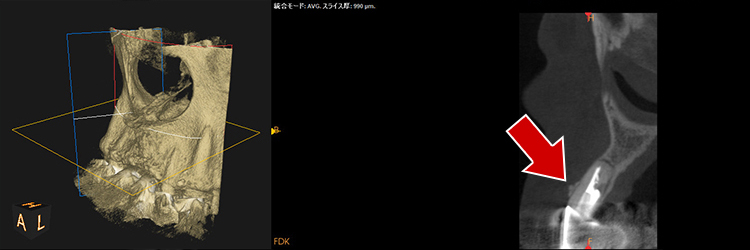

超最難関case(根尖病巣+パーフォレーション(術者のミス)

通常は「抜歯が当然」のcaseですが抜歯なしで治療成功事例

右下の画像が一番変化を診る上で基準となる画像でして(CT)、根の先端の病気が減っていること、白く濃く映った根のお薬がしっかりと入っている事が分かると思います。根の途中の黒い穴は、最初のドクターが謝って穴をあけてし合った後です。こういった高度な治療もセカンドオピニオンとしてお受けしております。

治療前

治療中

治療1年後

治療後3年後

レントゲンで施術前と施術後の比較

・赤色の部分→ドクターのミスをした箇所になります「パーフォレーション」

→結果、、、そこから病気ができています。。。

→通常はこれだけで「抜歯」となります。。。

・黄色の部分が根尖の病巣です。

→この原因でも抜歯となることもあります。

こちらの症例に関しても抜歯するくこともなく、治療成功となります。